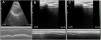

We measured the DSF of the right diaphragm in the zone of apposition using a portable multifrequency linear transducer that was placed longitudinally on the right anterior axillary line between the seventh and eighth intercostal space.5 DSF was 40%, so we were confident that the risk of complications would be very low (Fig. 1). While the patient's characteristics did not suggest a particularly high risk, the clinical evaluation performed with predictive scales for postoperative complications indicated a moderate risk (6.6%) of myocardial infarction, pulmonary edema, ventricular fibrillation, and cardiac arrest, and a very high risk (42.1%) of perioperative pulmonary complications according to the ARISCAT scale,4 the clinical scale that we routinely use for PE. A very high risk on the ARISCAT scale prompts us to perform other pre-surgery evaluations; however, in this case the decision was made on the basis of the DSF. This finding was reported to the cardiovascular surgeon and the decision was made to schedule surgery. DSF 24h after surgery was 38%.2 The patient had no immediate cardiopulmonary complications, was extubated early, left the intensive care unit on the third day, and showed very good postoperative progress.

(A) Diaphragmatic dome in 2D and anatomical M modes with convex transducer showing displacement of the dome in vital capacity. (B) Diaphragm in zone of apposition with linear transducer and measurement of thickness in maximum expiration. (C) Diaphragm in zone of apposition with linear transducer and measurement of thickness in minimum expiration. (B and C) For calculation of preoperative shortening fraction.